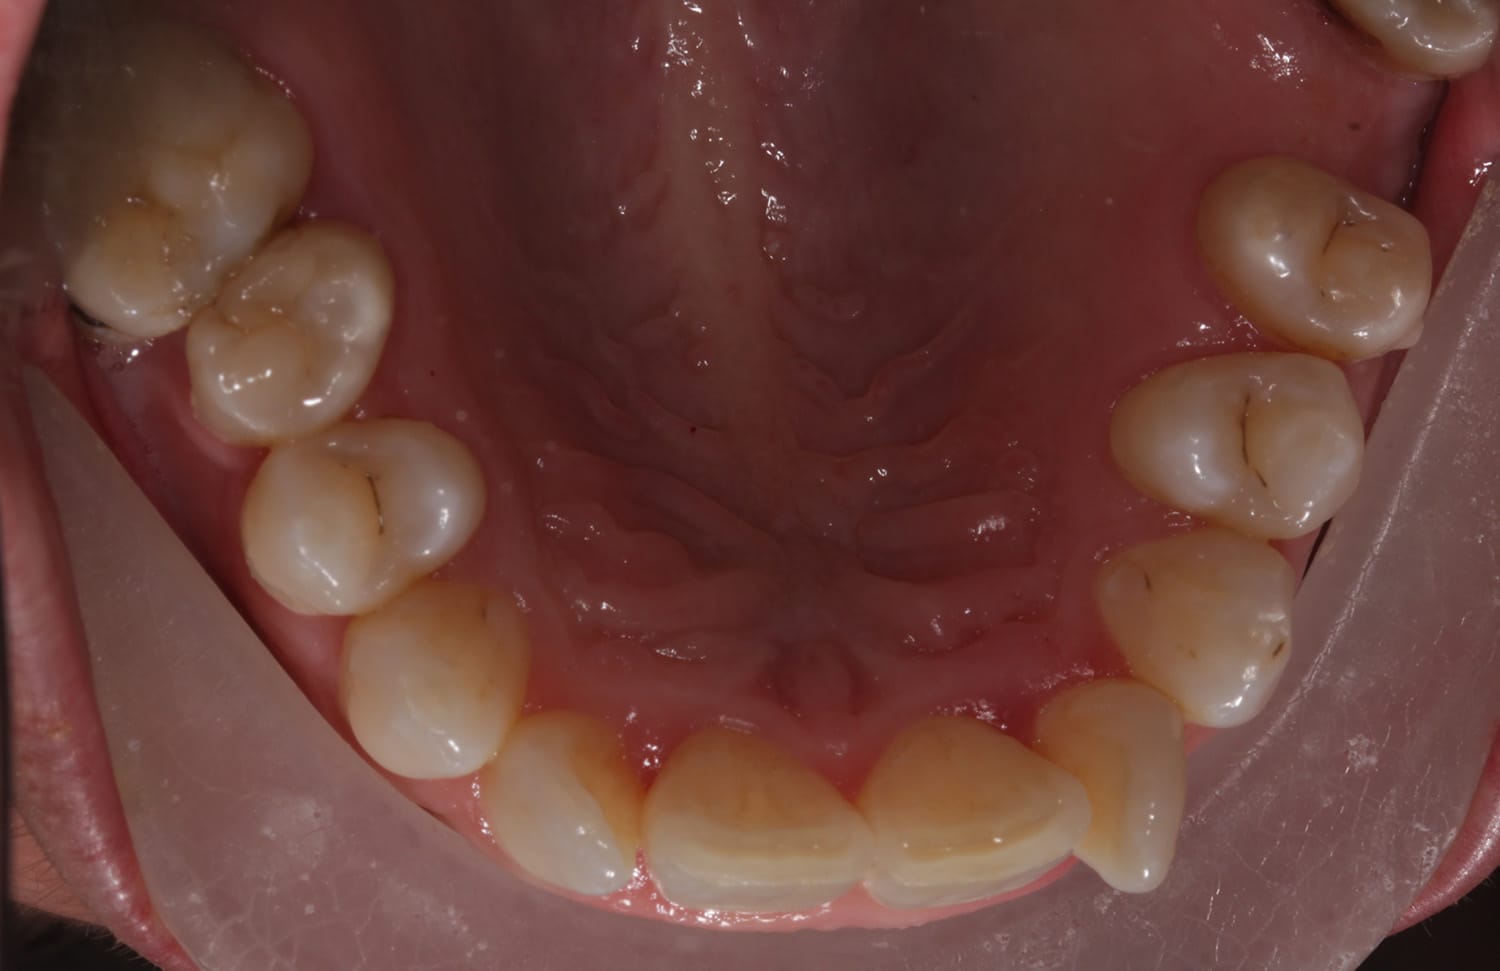

Our patient shares her treatment experience below, highlighting the confidence her new, straighter smile has given her.

(Treatment time : 8 months)

“Before I was always conscious of the appearance of my teeth and would sometimes be hesitant to smile”

“It is simply amazing! I am proud of my new beautiful smile!”

“No more worrying about my wonky smile. I smile with pride.”